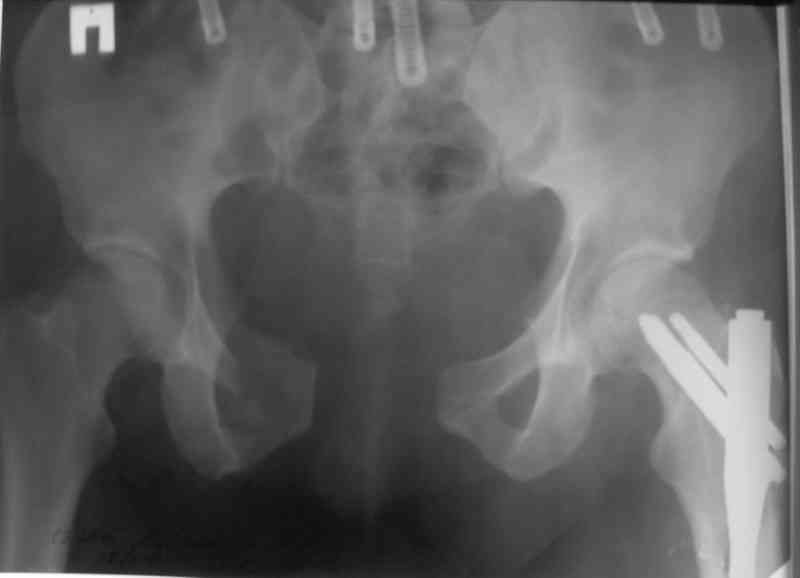

Я помню технику транссакральной фиксации тазового кольца длинными 5 мм Шанцами - повреждения типа В, в этом же случае задний отдел тоже вовлечен

т.е комбинированная нестабильность, поэтому вопрос - достаточно ли только двух Шанцев для стабилизации таза? Что вы думаете об anterior Right SI joint plating + tension band plating from the back.?

PS после фиксации бедра под Эопом посмотрел инлет и аутлет проекции, насколько репонируемо смещение правой половины таза *невооруженными*

руками - никаких шансов улучшить позицию иначе бы конечно воспользовался длинными Шанцами сразу после бедра.

Элегантная фиксация, поздравляю.Но ваш случай : одноплоскостная горизонтальная нестабильность Tyle B2.2 отличен от представленного мной - у

моего больного + вертикальная нестабильность за счет повреждения правого крестцово-подвздошного сочленения и перелома заднего отдела подвздошной

кости- С2 тип. Поэтому и возникла дилемма : выбор оптимальной фиксации заднего отдела:

По-поводу фиксации таза спонгиозными винтами. Данный способ все-таки показан для фиксации повреждения крестцово-подвздошного сочленения или переломов крестца. Мне кажется, что в данной случае ситуация иная - имеется перелом "основания" крыла подвздошной кости (в который вовлечена и поверхность, составляющая крестцово-подвздошное сочленение). Не уверен, что фиксация данного повреждения (и заднего полукольца) винтами будет стабильной, так как именно на уровне 1-2 крестцовых позвонков (где обычно вводят винты) линия перелома уходит в латеральном направлении от крестцово-подвздошного сочленения.

По-поводу репозиции костей таза. Производить репозицию костей все-таки необходимо. Пока я не встретил информации, сколько времени прошло с момента травмы, но одномоментно низвести правую половину таза может быть тяжело, учитывая и наличие перелома бедренной кости (что затруднит тракцию за нижние конечности).